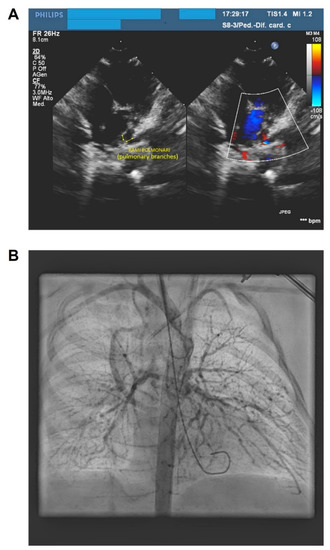

2. Case Presentation